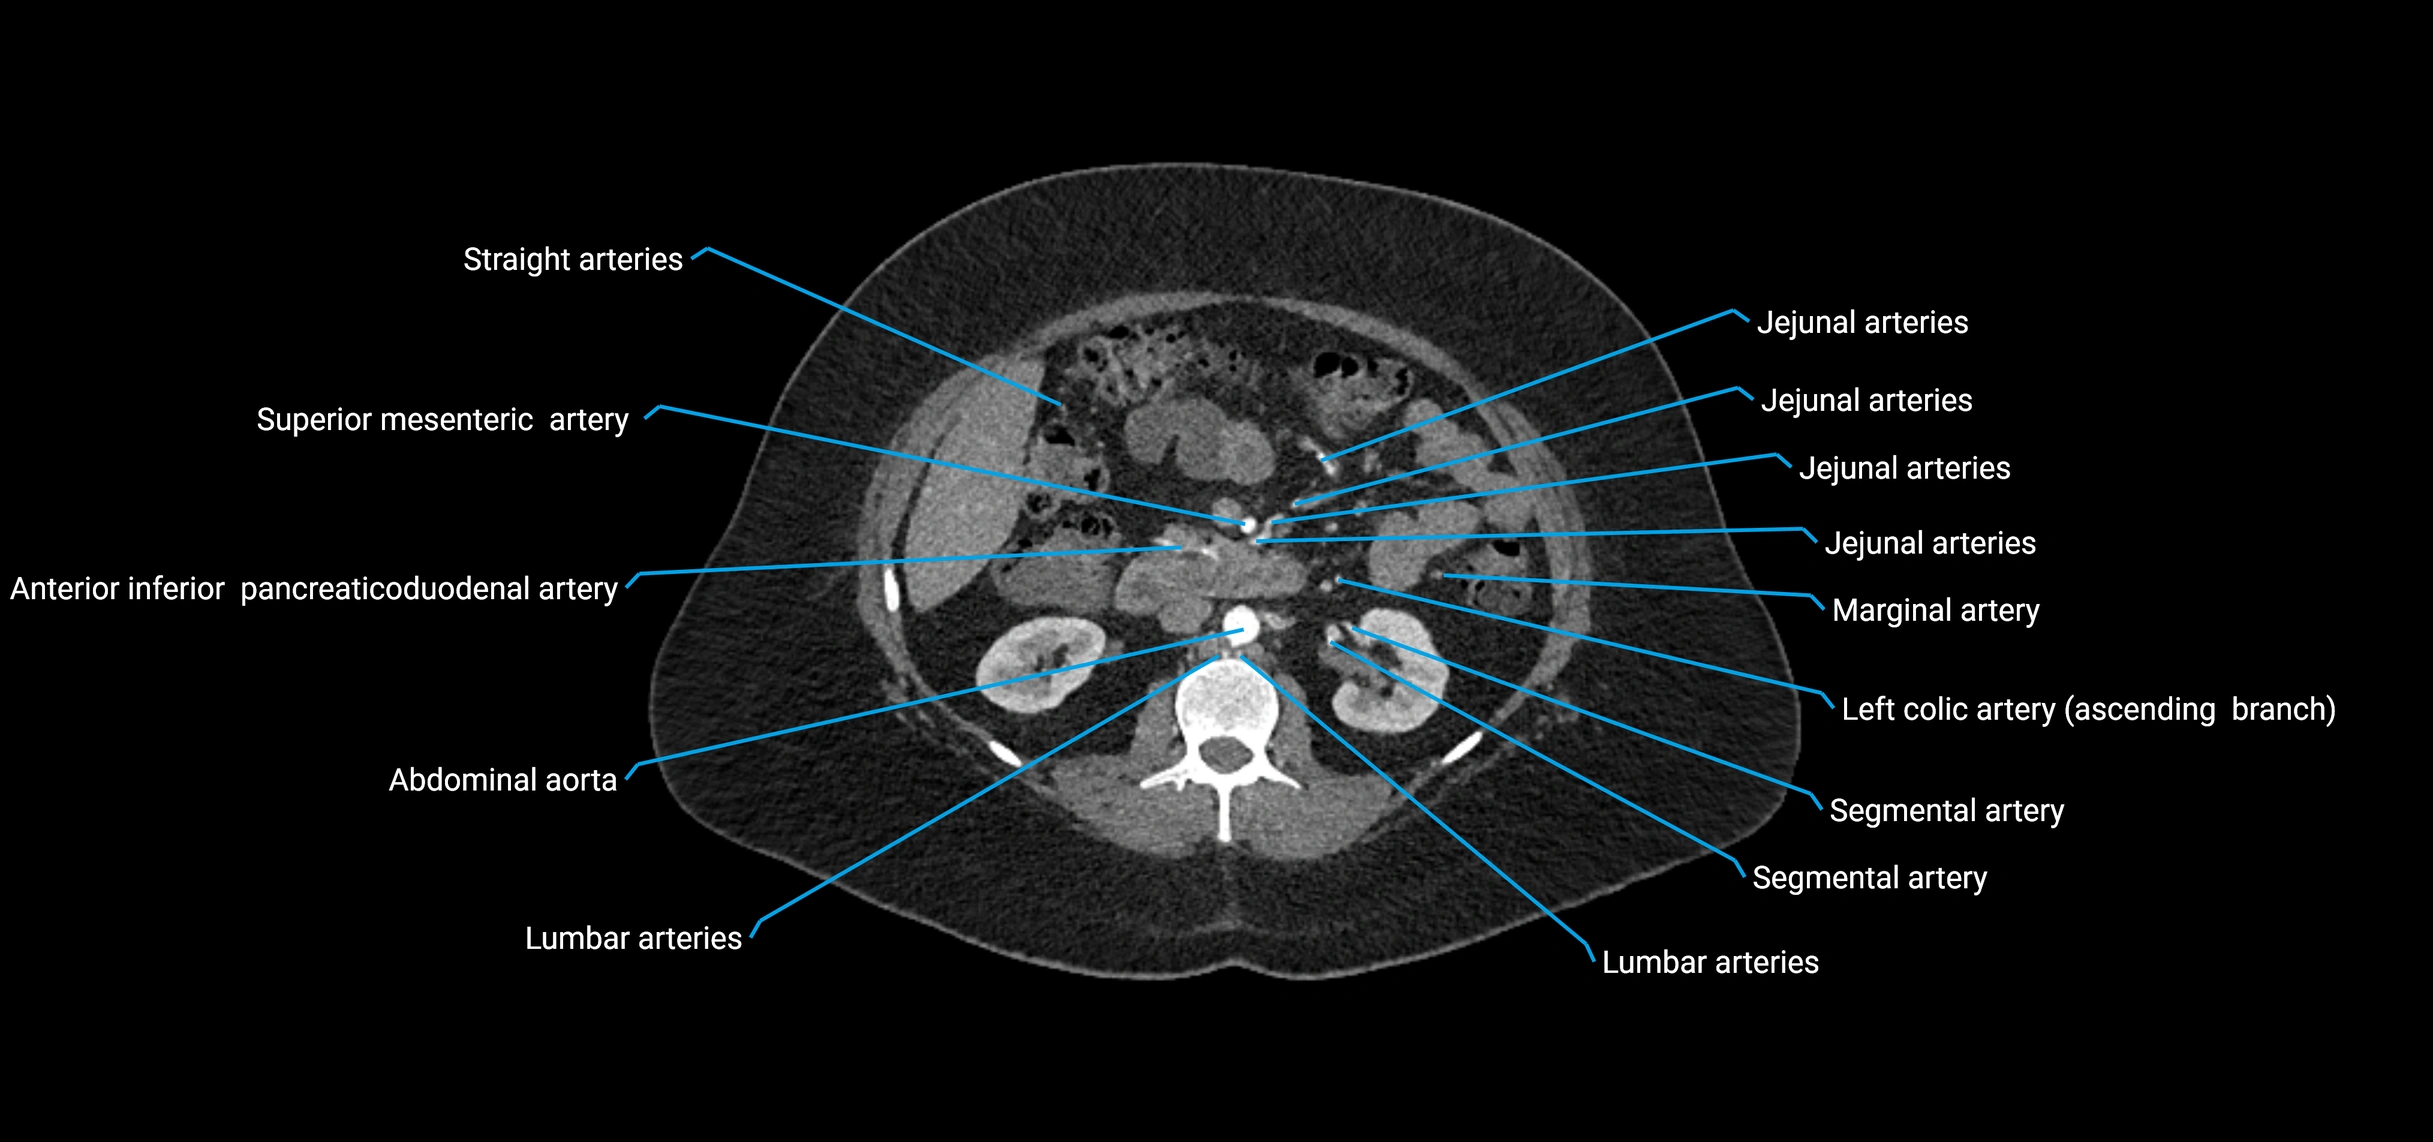

CT Appearance

Non-contrast CT:

• Appears as a tubular soft tissue structure anterior to vertebral bodies

• Calcified atherosclerotic plaques appear as hyperdense foci along the wall

• Useful for screening abdominal aortic aneurysm (AAA) size and mural calcification

Contrast-enhanced CT (CTA):

• Gold standard for abdominal aortic imaging

• Provides excellent detail of lumen, wall, aneurysm, thrombus, and branch vessels

• Multiplanar and 3D reconstructions help in aneurysm measurement, stent graft planning, and dissection evaluation

• Detects acute rupture, traumatic injury, or occlusion with high sensitivity

CT images

image